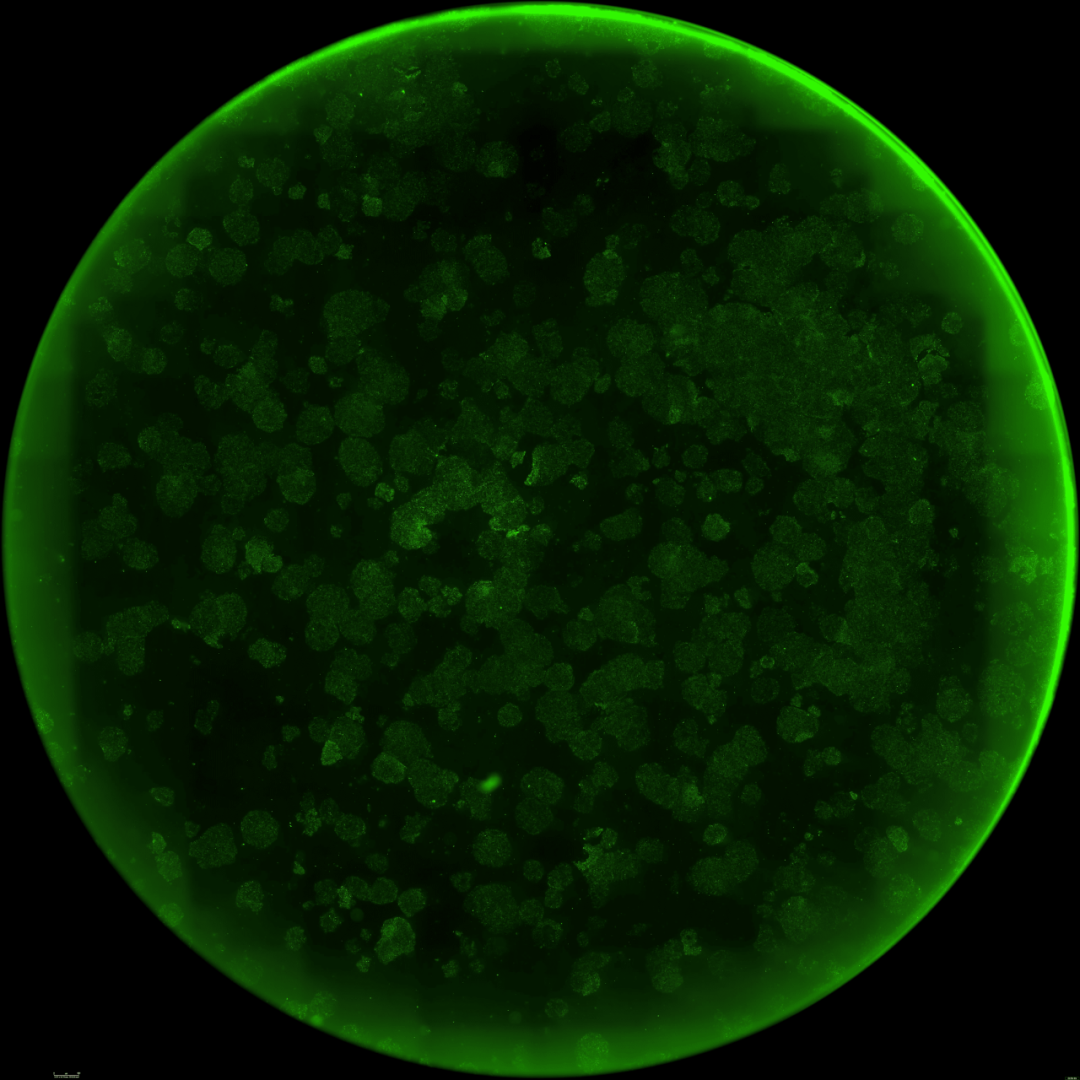

为了进一步确认重编程效率的提升并探索其临床应用潜力,研究团队测试了一种新的递送方式(使用mRNA替代病毒载体)和另一种细胞类型——源自三位中年(50岁以上)捐赠者的人类间充质基质细胞(MSCs)。

仅7天内,便有超过30%的细胞开始表达关键的多能性标记物(SSEA4和TRA-1-60)。

到第12天,已出现大量形态与典型iPSC相似的集落。这些细胞中超过85%激活了包括OCT4、NANOG、SOX2和TRA-1-60在内的关键干细胞标记物的内源性表达。

接着,研究团队验证了这些由RetroFactor衍生的iPSC能够成功分化为全部三个主要胚层(内胚层、外胚层和中胚层)。

此外,研究团队将多个单克隆iPSC细胞系传代培养,证实了其具有健康的核型和适用于细胞疗法的基因组稳定性。

这些结果全面超越了由合同研究组织(CRO)使用标准因子生成的常规iPSC细胞系的基准数据,进一步证明了研究团队工程化变体的稳健性,也为其在不同递送方式和细胞类型中的应用提供了有力证据。

下面三张图中所有的结果共同证实了,研究团队已成功获得健康、且完全重编程的干细胞,从而也全面验证了重编程干细胞的健康与功能。